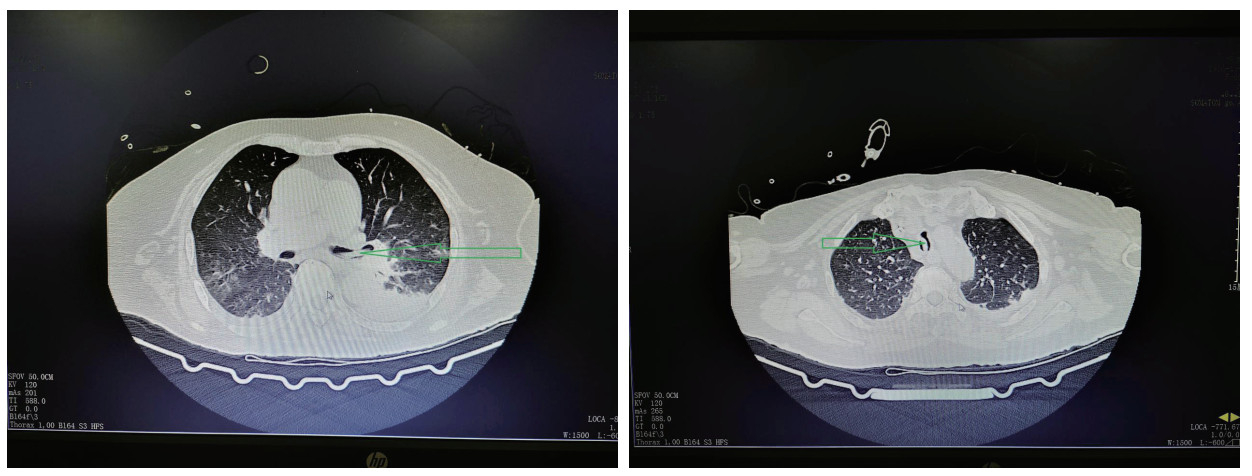

入院辅助检查:急诊血常规:“白细胞计数: 87.5×109/L,中性粒细胞计数: 27.6×109/L,占比31.5%,血小板计数: 673×109/L,淋巴细胞计数:55.8×109/L,占比63.8%,嗜酸性细胞计数: 0.00×109/L,单核细胞计数:3.9×109/L,超敏C反应蛋白:97.0 mg/L”。血气分析:“pH: 7.4,PaO2: 48 mmHg,PaCO2: 30.5 mmHg,SatO2: 83%,BE: -5 mmol/L,乳酸:2.5 mmol/L”。急诊生化常规:“血钠133 mmol/L,肌酐207 μmol/L”。胸部CT平扫(见图 1):“①两肺支气管扩张伴少许感染灶;②两肺散在实性结节;③纵隔、两肺门及腋下多发淋巴结”。头颅CT未见明显异常。

| 图 1 抢救室行胸部CT示气管及左右主支气管内未见异物 |

患者有明确高温暴露史,根据患者病史,查体及相关辅助检查,诊断“经典型热射病、Ⅰ型呼吸衰竭、支气管扩张伴感染、急性肾损伤”,继续予气管插管,呼吸机辅助呼吸,并每日监测气管插管气囊压力,迅速物理降温,抗感染,抗凝,补液扩容改善循环等对症治疗,经积极治疗后患者呼吸,循环等各项生命体征趋于稳定。患者白细胞明显高于正常值,且淋巴细胞占比明显增高,行骨髓穿刺活检后血液科专科会诊,诊断为“慢性淋巴细胞白血病,骨髓增殖性疾病”。患者住院2 d后开始出现阵发性呼吸困难,发作时伴大汗淋漓,夜间尤为明显,持续数分钟到数十分钟不等,症状发作时经皮血氧饱和度下降至90%,潮气量由约400 mL下降至约300 mL,两肺听诊可闻及少许哮鸣音,患者既往有慢性支气管炎病史,考虑支气管哮喘发作引起气道痉挛,应用甲基强的松龙针40 mg静脉注射,调整呼吸机参数,后患者呼吸急促逐渐缓解。入院第3天复查胸部CT(见图 2):“两肺感染性病变,右肺中叶、左肺上叶部分支扩伴感染,两侧胸腔少量积液伴邻近两肺下叶膨胀不全,气管及左侧支气管内条状高密度影”。根据胸部CT结果,气管及左侧支气管内高密度影考虑气道内痰液阻塞,加强翻身拍背,吸痰等对症治疗。入院第4天凌晨,患者再次出现呼吸急促,大汗淋漓,两肺听诊可闻及少许哮鸣音,经皮血氧饱和度下降至83%,潮气量明显下降至200 mL左右,血气分析提示:“PaO2:48 mmHg,PaCO2:30.5 mmHg,SatO2:83%,BE:-5 mmol/L,AB:18.5 mmol/L”。继续糖皮质激素应用缓解气道痉挛,鼓肺吸痰,上调呼吸机参数等综合治疗,0.5 h后患者氧合无明显改善,不排除气道梗阻可能,立即行床边纤维支气管镜检查,镜下见气管及左主支气管内有2条奶油色活动性虫体,给予夹出,夹出虫体后患者呼吸逐渐平稳,氧合明显改善(支气管镜下虫体图片详见图 3)。2条虫体为活虫,放置在生理盐水中可见活动,测量虫体长度约25 cm,虫体直径约5 mm(虫体全图详见图 4),经本院感染科及市疾控中心会诊后认定2条虫体为蛔虫成虫,故此,患者诊断“蛔虫病”明确,治疗上予阿苯达唑片400 mg/d鼻饲, 连续服用2日,驱虫治疗后5 d内大便中总共排出蛔虫成虫12条,驱虫治疗效果显著,病情好转。

| 图 2 入院后3 d,胸部CT示气管及左侧支气管内异物(绿色箭头所指为蛔虫虫体) |